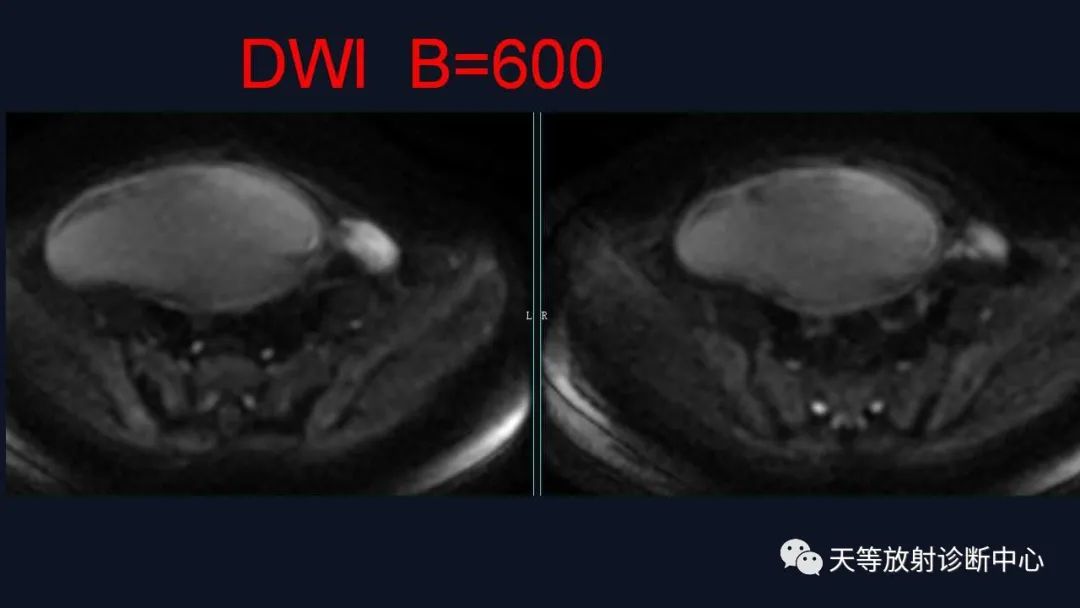

1、浆液性囊腺瘤 :浆液性囊性肿瘤较常见,浆液性肿瘤好发的平均年龄为40岁以上,表现为纯囊性,可呈多囊改变,T1WI呈低信号、T2WI呈高信号、DWI呈低信号,增强后无实性成分强化。

交界性肿块呈囊实性、多房改变, T1WI呈高信号、T2WI呈高信号、病灶实性部分DWI以较高信号为主,增强后实性成分均呈结节状强化。